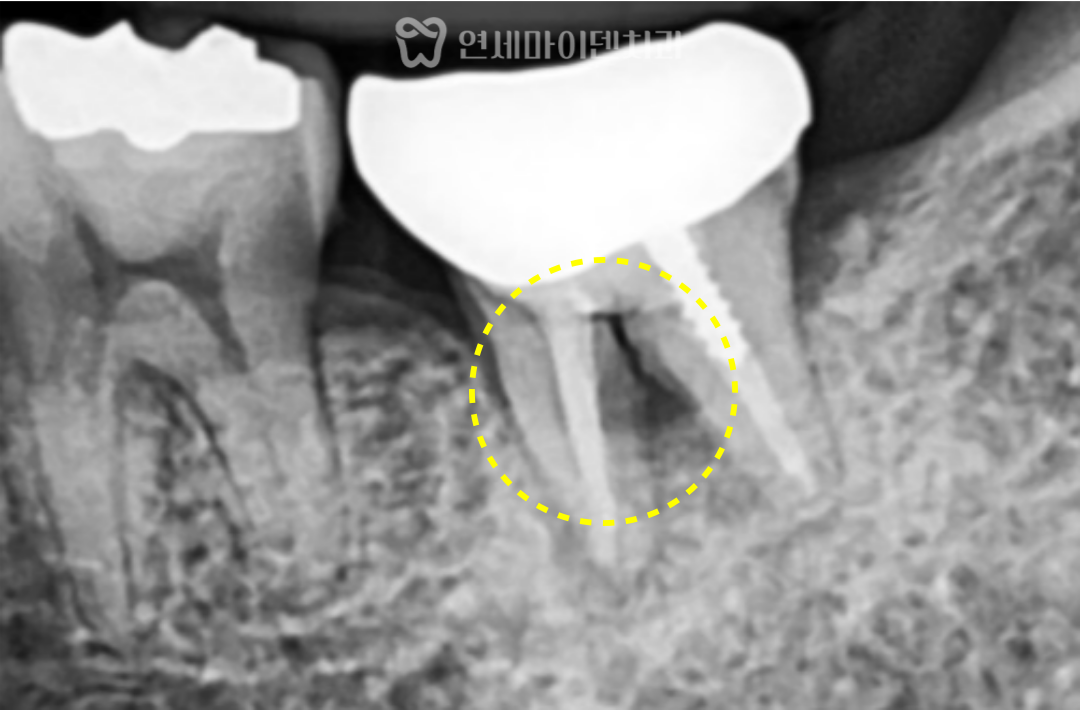

분지부 뼈가 녹는 원인

치아 뿌리 사이의 분지부 뼈가 녹는 경우는

예후가 좋지 않은 경우가 많습니다.

대표적인 원인은 다음과 같습니다.

치주질환으로 인해

잇몸과 뼈가 서서히 파괴되는 경우

치아 뿌리에 금이 가는

수직 치근 파절

그리고 치료 과정에서

비정상적인 통로가 생긴 경우입니다.

이번 케이스에서는

과거 신경치료 과정 중

치아 내부에 불필요한 구멍이 생겼고,

이를 적절한 재료가 아닌

레진으로 덮어 마무리하면서

문제가 시작된 것으로 보였습니다.

레진은 이러한 부위에서

완전한 밀폐를 유지하기 어려워

시간이 지나면서 미세한 틈이 생기고,

그 틈을 통해 세균이 유입되면서

결국 분지부 뼈까지 녹게 되는 결과로

이어진 것입니다.